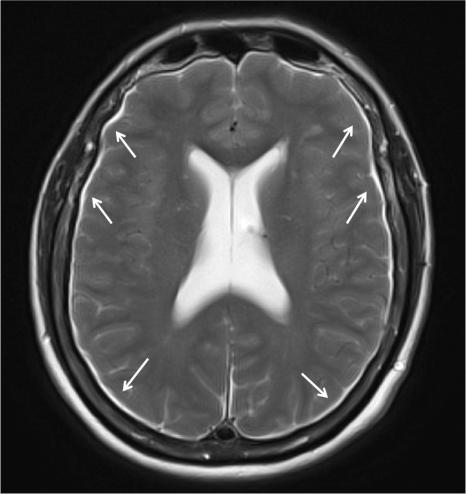

En la Imagen 2, se observan los higromas subdurales por disminución de la presión de LCR. En otras ocasiones, se pueden producir hematomas subdurales por rotura de las venas puente.